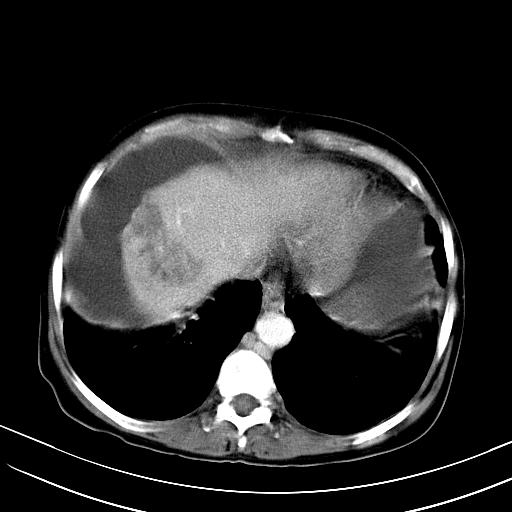

1)肝右叶肝癌并肝动静脉漏。2)肝硬化,腹水。3)胆囊炎。

肝右叶肝癌并动静脉漏,肝硬化,腹水。

1)肝右叶肝癌并肝动静脉漏 门v右支瘤栓伴海绵样变。2)肝硬化,脾大 腹水。3)胆囊炎。门v高压.

右叶肝癌并肝动静脉漏(动脉期肝动脉及门静脉内均可见造影剂),肝硬化,腹水。(胆囊壁水肿)

1)肝右叶肝癌,考虑并发肝动静脉漏。扫描时间好像慢了。2)肝硬化,门脉高压、脾大、腹水。